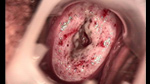

婦科leep錐切手術(shù) CIN2-3

• CIN 2-3 碘著色后CIN 2-3 碘著色后